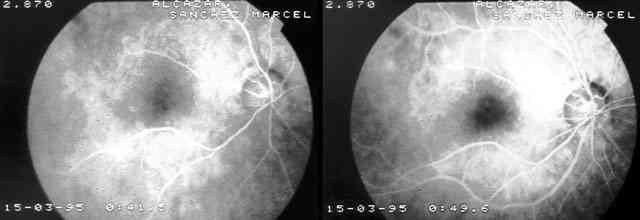

Figuras 2 y 3

CASO 1: 4 DÍAS POST-INYECCIÓN PERIBULBAR. NORMAL RELLENO COROIDEO PERO CON RETRASO MARCADO DEL RELLENO ARTERIAL Y UN INCREMENTO DEL TIEMPO DE TRÁNSITO ARTERIO-VENOSO.